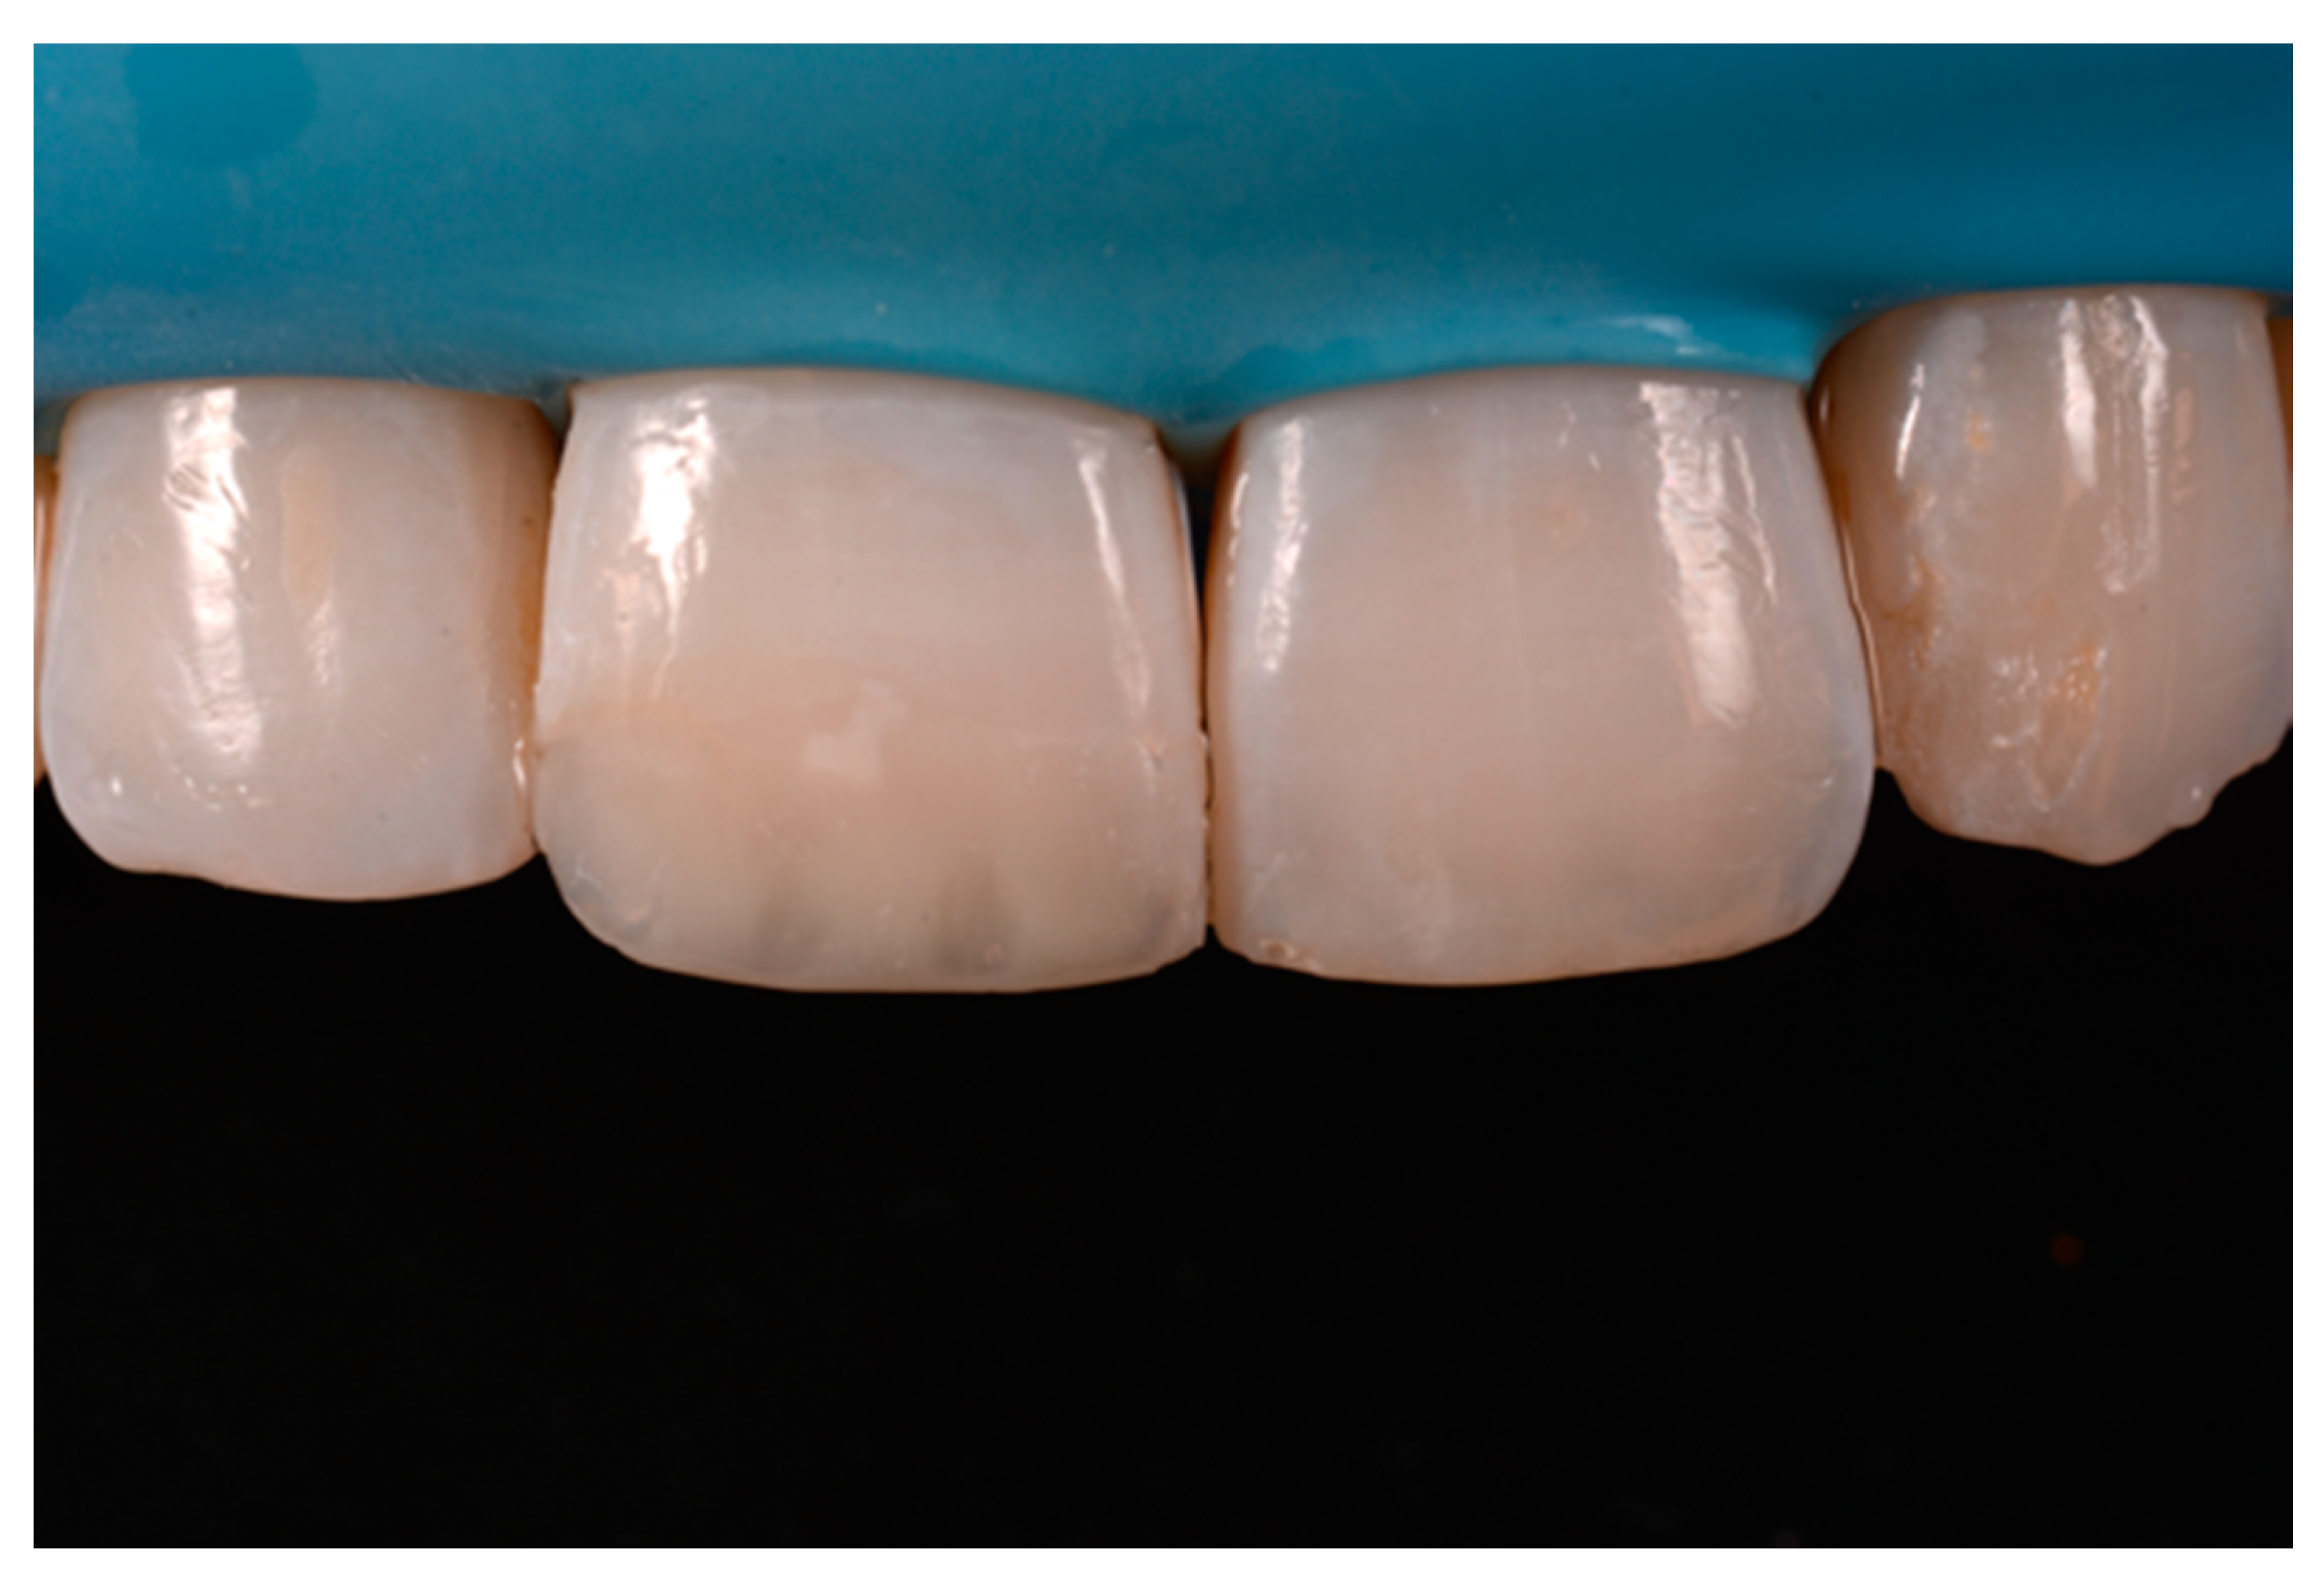

A healthy 38-year-old man referred to the dental office for the esthetic rehabilitation of left central maxillary incisor (Figure 41). Shade was selected as described in previous cases, using the button-try technique [14]. Isolation, preparation (Figure 42) and adhesive procedures were performed (Tokuyama Bond Force, Tokuyama Dental, Osaka, Japan). and Class III was restored on right central incisor (Asteria, A2B, Tokuyama Dental, Osaka, Japan). Frame was then completed on #2.1 (Figure 43) with the use of posterior sectional matrices using translucent and body material (Asteria, NE, A2B Tokuyama Dental, Osaka, Japan). After removing excesses both from the incisal margin and from the interproximal portion (Figure 44) silane and adhesive was applied strictly following the procedure described in Section 2.1.2. Dentinal body (Asteria, A2B, Tokuyama Dental, Osaka, Japan) was applied to reproduce internal anatomy (Figure 45) and then the external translucent enamel (Figure 46) (Asteria, NE, Tokuyama Dental, Osaka, Japan) was applied. The restoration shows good integration 6-months post-operative (Figure 47).

The frame completed.

The frame modified either in the incisal frame and in the interproximal wall.

Dentinal body with space left for translucencies.

External enamel layer is applied.

Six months post-operative.